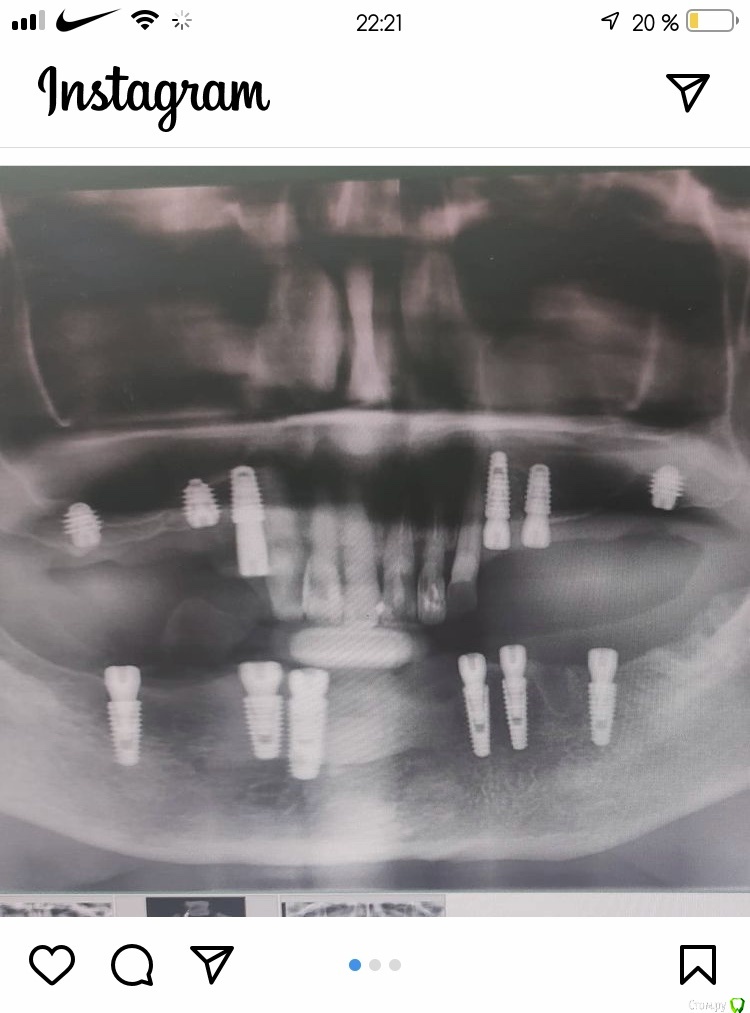

Женька Опубликовано 25 ноября, 2020 Поделиться Опубликовано 25 ноября, 2020 И возвращаясь, к вашим картинкам @Марья Моревна, есть ведь и такие работы. И наверняка протезируется и стоит долго. Ссылка на комментарий